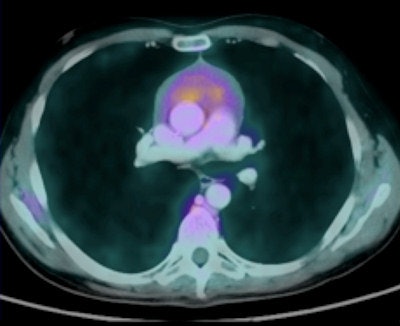

Differences in breathing patterns between CT and PET exam imaging can cause misregistration of pulmonary nodules on fused images, particularly at the lung bases. CT scans of the thorax are generally performed during a breath-hold, while PET images are acquired during tidal breathing. The authors recommend that acquiring CT images of the thorax during quiet respiration will help reduce artifacts.